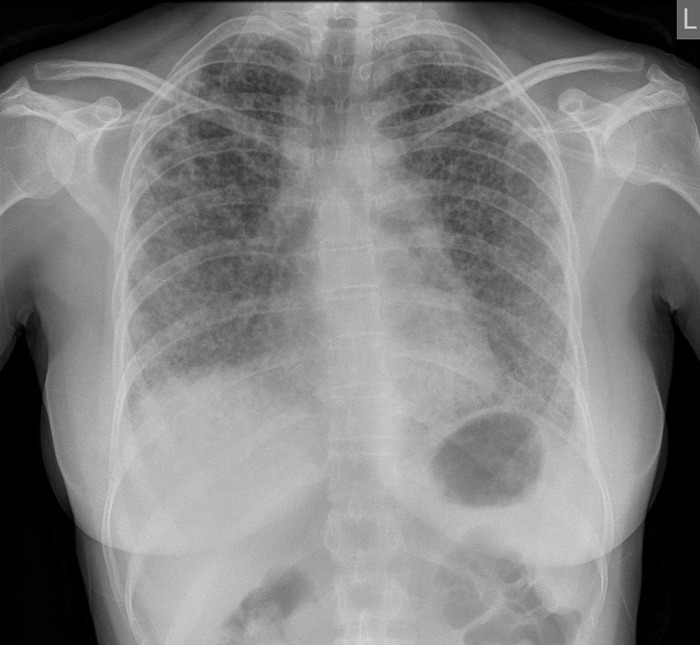

Расшифровка цифровых кодов флюорографии с примерами

01 - Кольцевидная тень (полость).

02 - Затемнение в легочной ткани (инфильтрация,ателектаз, округлая тень, среднедолевой синдром и др.).

03 - Очаговые тени в легочной ткани.

04 - Расширение тени средостения, в том числе увеличение размеров корня.

05 - Плевральные выпоты.

06 - Фиброзные изменения в легочной ткани (выраженные).

07 - Фиброзные изменения в легочной ткани (ограниченные).

08 - Повышение прозрачности легочной ткани (эмфизема локальная и распространенная).

09 - Изменения плевры (сращения, плевральные наслоения, обызвествления) выраженные.

10 - Изменения плевры (сращения, плевральные наслоения, обызвествления) ограниченные.

11 - Петрификаты крупные в легочной ткани - множественные (5 и более).

12 - Петрификаты крупные в корнях - множественные (5 и более).

13 - Петрификаты мелкие в легочной ткани - множественные (5 и более).

14 - Петрификаты мелкие в корнях - множественные (5 и более).

15 - Петрификаты крупные в легочной ткани - единичные.

16 - Петрификаты крупные в корнях - единичные.

17 - Петрификаты мелкие в легочной ткани - единичные.

18 - Петрификаты мелкие в корнях - единичные.

19 - Изменения диафрагмы, не связанные с плевральной патологией (диафрагмальная грыжа, высокое стояние диафрагмы и т. д.).

20 - Состояние после операции на легком.

21 - Изменения скелета грудной клетки (сколиоз, кифосколиоз, костная мозоль, добавочное ребро, остеофиты и т. д.).

22 - Инородное тело (проецируется на легочную ткань, тень средостения в мягких тканях).

23 - Сердечно-сосудистая патология.

24 - Прочие - добавочная доля.

25 - Норма.

26 - Брак.